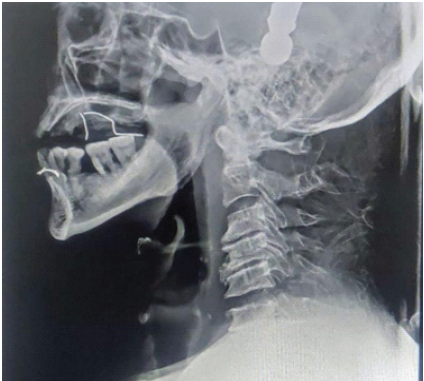

Sensory examination showed reduced sensation over the upper-limb dermatomes (C5–T1), whereas all sensations were preserved in the lower-limb dermatomes (L2–S1). Sacral sensory sparing was present, and the bulbocavernosus reflex was intact, confirming an incomplete injury. Deep tendon reflexes and muscle tone were normal. The patient was classified as ASIA impairment scale grade D, consistent with CCS. The patient presented with quadriparesis, with upper limb weakness more pronounced than lower limbs and reduced motor power and sensation in the upper limbs (Left > Right). The findings are suggestive of CCS. A plain radiograph of the cervical spine showed C5–C6 fracture dislocation (Fig. 2).

Figure 2: Cervical spine X-ray showing C5–C6 fracture dislocation